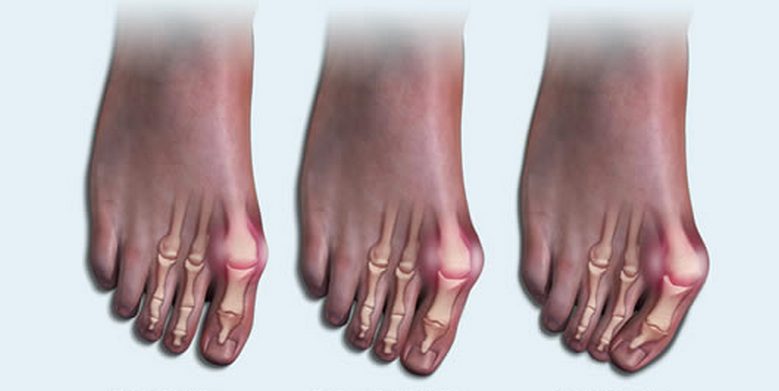

Клинически артрит стопы проявляется болью, ограничением движений, гиперемией, отечностью мягких тканей. При отсутствии врачебного вмешательства прогрессирующая патология становится причиной деформации суставов, частичного или полного анкилоза. На начальных этапах развития артрита стопы используются консервативные методы лечения. А при необратимых изменениях в хрящевых и костных тканях требуется проведение хирургической операции.

Подвижность стопы ограничивается, уменьшается объем, амплитуда движений. К этому приводит формирование остеофитов (костных наростов). Человек и сам намеренно избегает делать полноценный упор на стопу, чтобы не спровоцировать появления болей. Это становится причиной изменения походки.

Общими для всех видов артрита стопы ведущими симптомами являются боль, деформация суставов, нарушение функций. Но для каждой формы патологии характерны специфические признаки. На начальном этапе болевой синдром выражен слабо, но постепенно его интенсивность повышается. Боль может эпизодической, но чаще она становится постоянной, усиливается при ходьбе, сгибании, разгибании, вращении стопы.